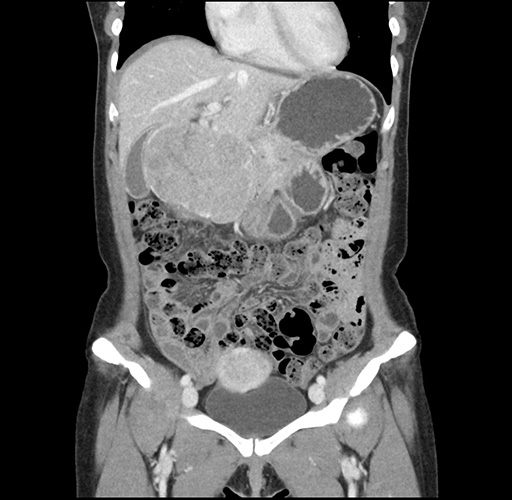

Imaging Analysis

Look through the patient's CT scan to identify any areas of concern for the necessary procedure.

Based on your CT findings, which issue(s) would give reason for "planned slowing down moment(s)" in this case?